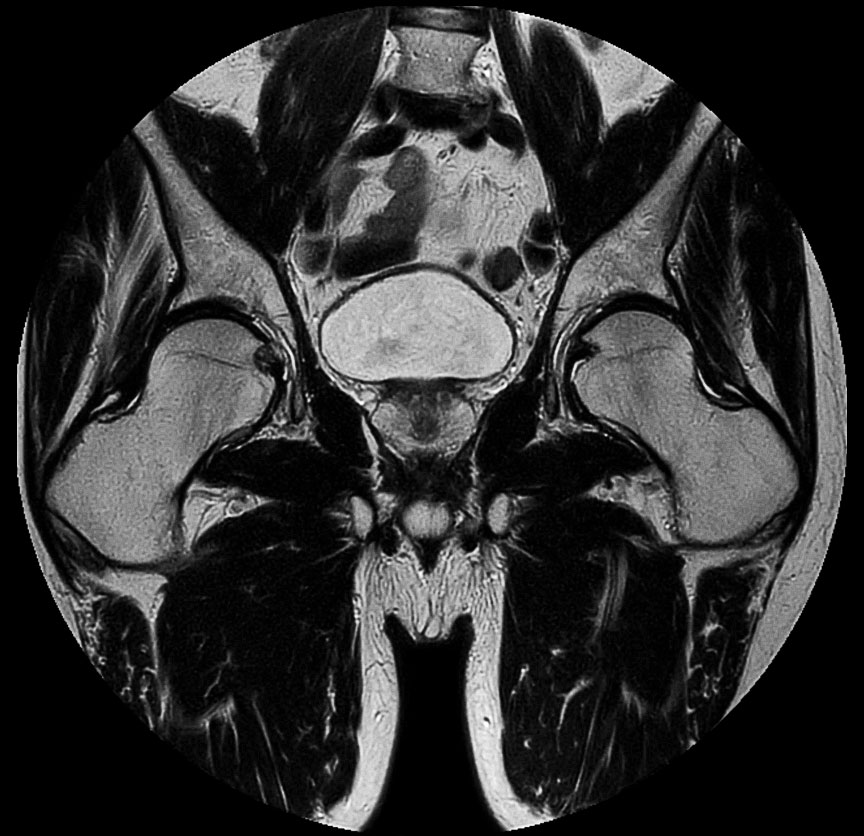

Prostate imaging

• Clinical Application